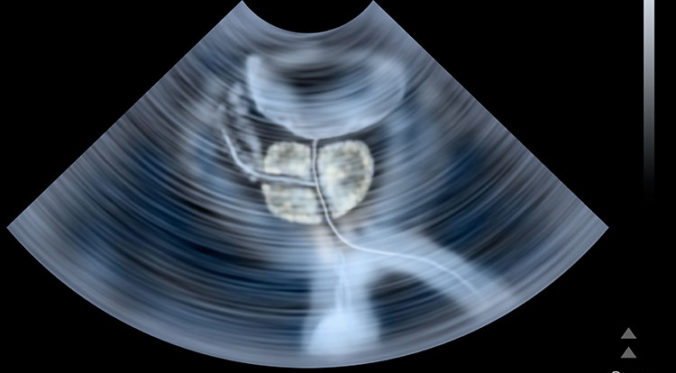

Two months later, I had a prostate biopsy. I’ve never had one and really didn’t know what to expect. Well, let me tell you it is not pleasant. The doctor takes a sampling probe through your back door. He samples the prostate by puncturing the colon into the gland. Not once… six times.

Pathology report now said that I had early prostate cancer. They use something called the Gleason Score. I was at a six which is typical of early stage cancer.